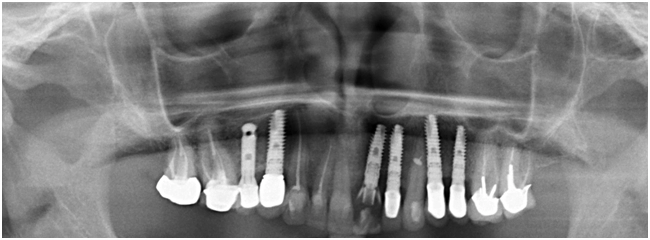

Завершающий этап лечения.

Через 6 месяцев проведен контрольный осмотр. Вокруг временной реставрации сформирован безупречный контур десны, соответствующий естественному зубу за счет поддержки мягких тканей десны в период остеоинтеграции имплантата.

Десневой сосочек и краевая десна без признаков воспаления.

Сделан слепок для изготовления постоянной ортопедической конструкции.

Через 1 неделю зафиксировали постоянную коронку на имплантат.

Через 2 года.

Клинически и рентгенологически имплантат остается стабильным. Ортопедическая реставрация состоятельной.